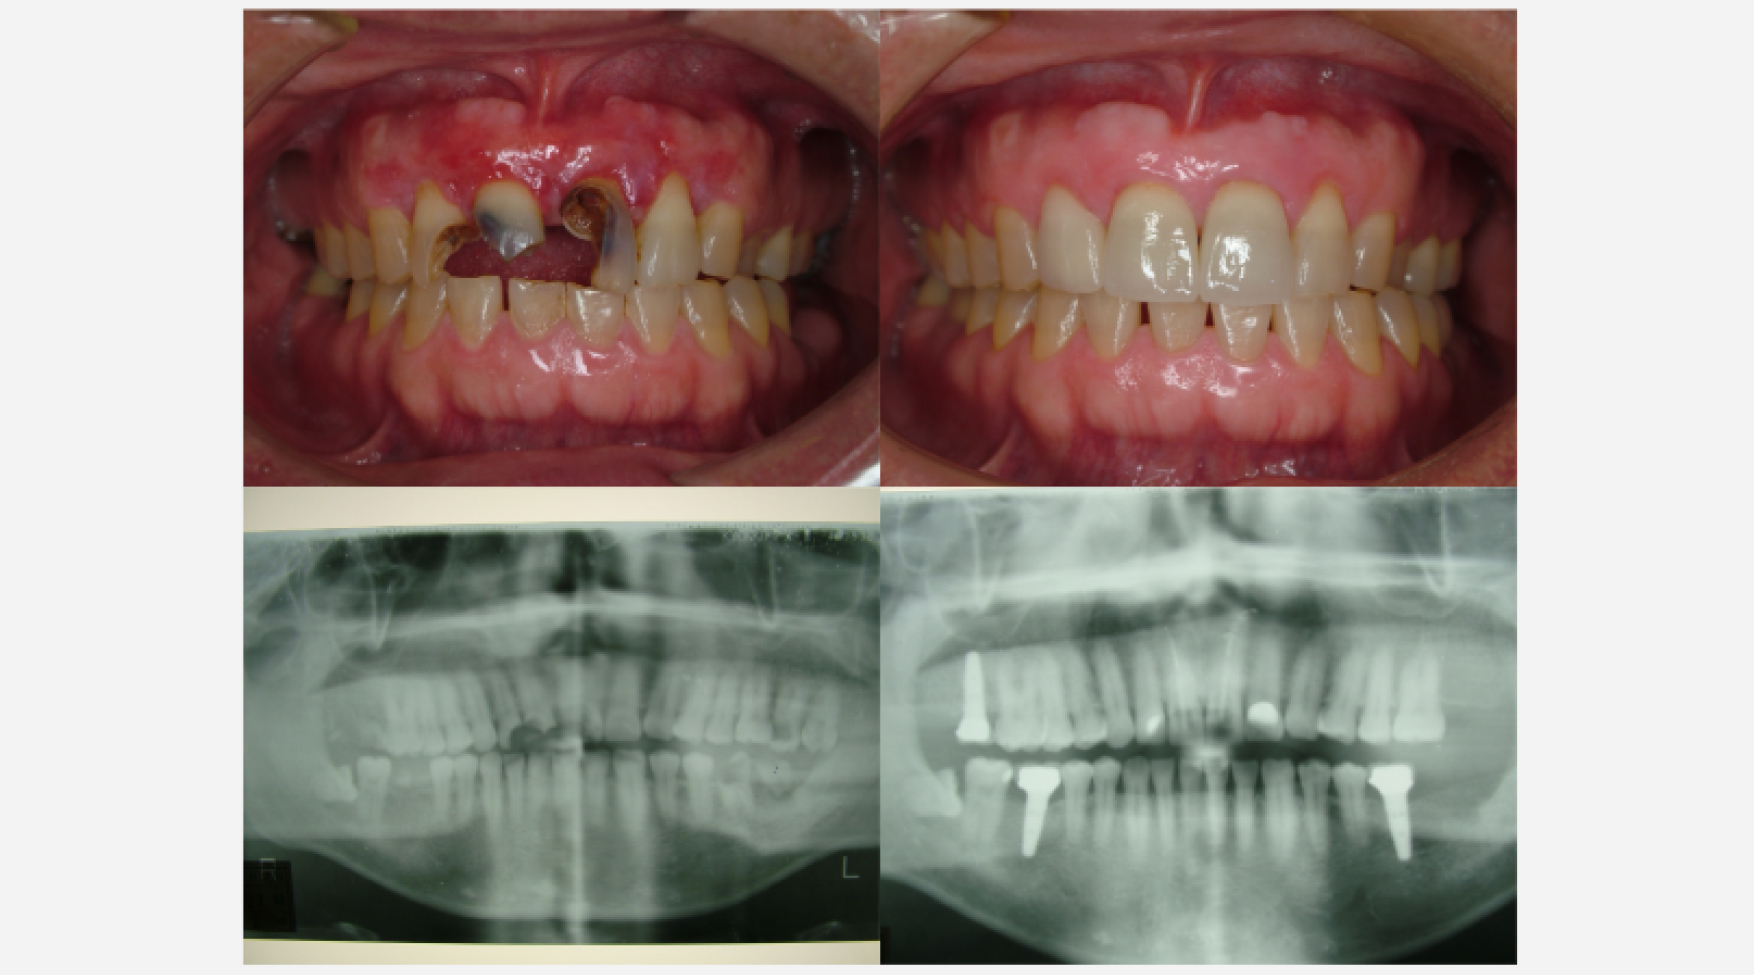

治療前

治療経過

術後3ヶ月 仮歯装着

術後1年後

治療前と治療後

| 治療内容 | 歯周外科:歯肉弁根尖側移動術 (Apically Positioned Flap Operation) |

|---|---|

| 患者様の年齢 | 35歳 |

| 患者様の性別 | 男性 |

| 治療期間 | 初診時より2年 |

| 治療回数 | 矯正治療合わせて85回程度 |

| 治療費用 | インプラント:150万円/歯周外科:3万円/補綴治療:50万円 |